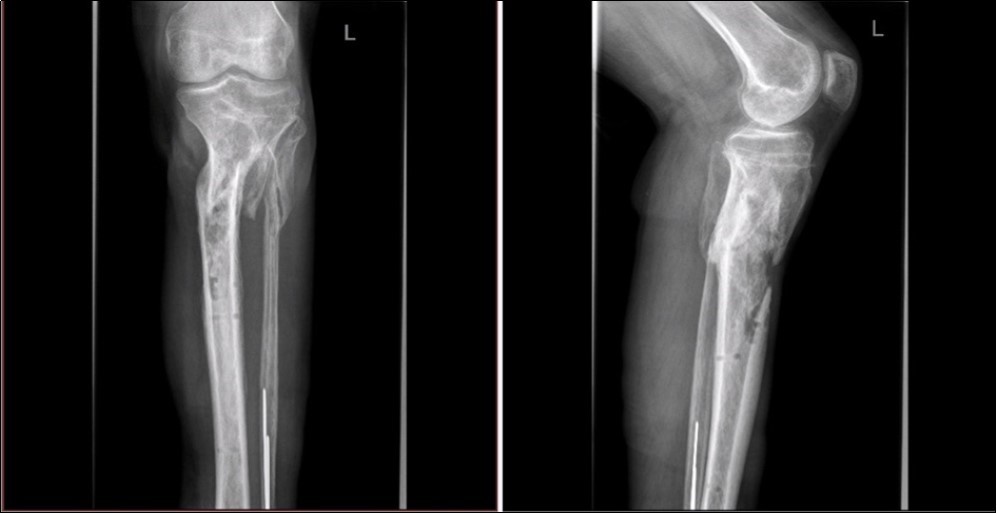

Figure 3.22 January – primary X-ray oblique splinter fracture of the tibia shaft

Figure 4.Debriteman and removal of macroscopic impurities Fracture stabilization using external fixator Reconstruction of soft tissue, subcutis and skin, necrectomy Installation of flushing lavage Covering defects with artificial skin – Syncryt

Figure 5.22 January – primary X-ray - Fracture stabilization using external fixator

Figure 6.22 January – primary X-ray - Fracture stabilization using external fixator